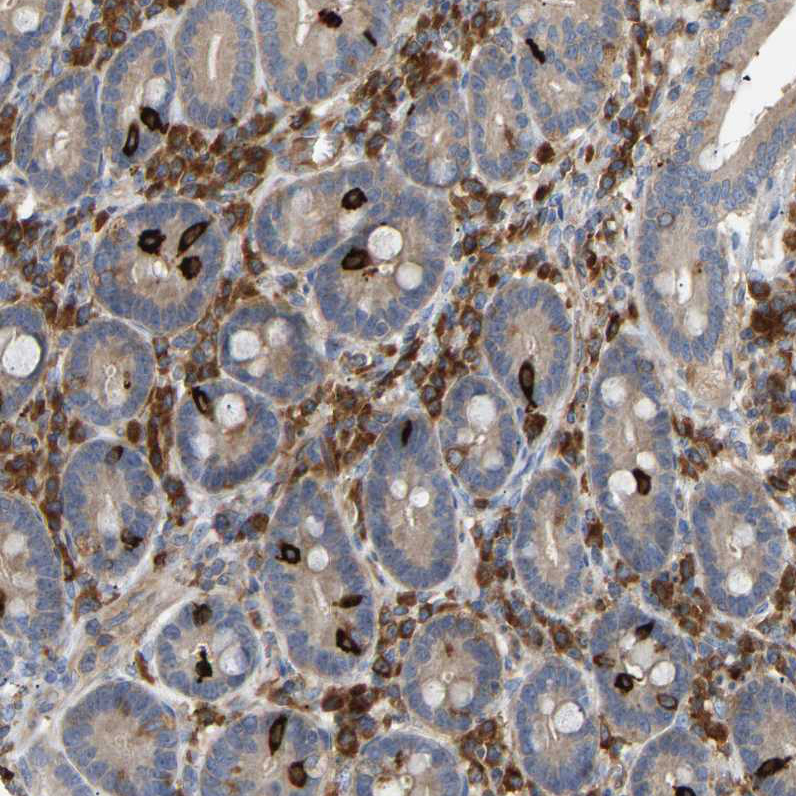

Immunohistochemistry analysis in human lymph node and pancreas tissues using HPA020100 antibody. Corresponding PLCG2 RNA-seq data are presented for the same tissues.